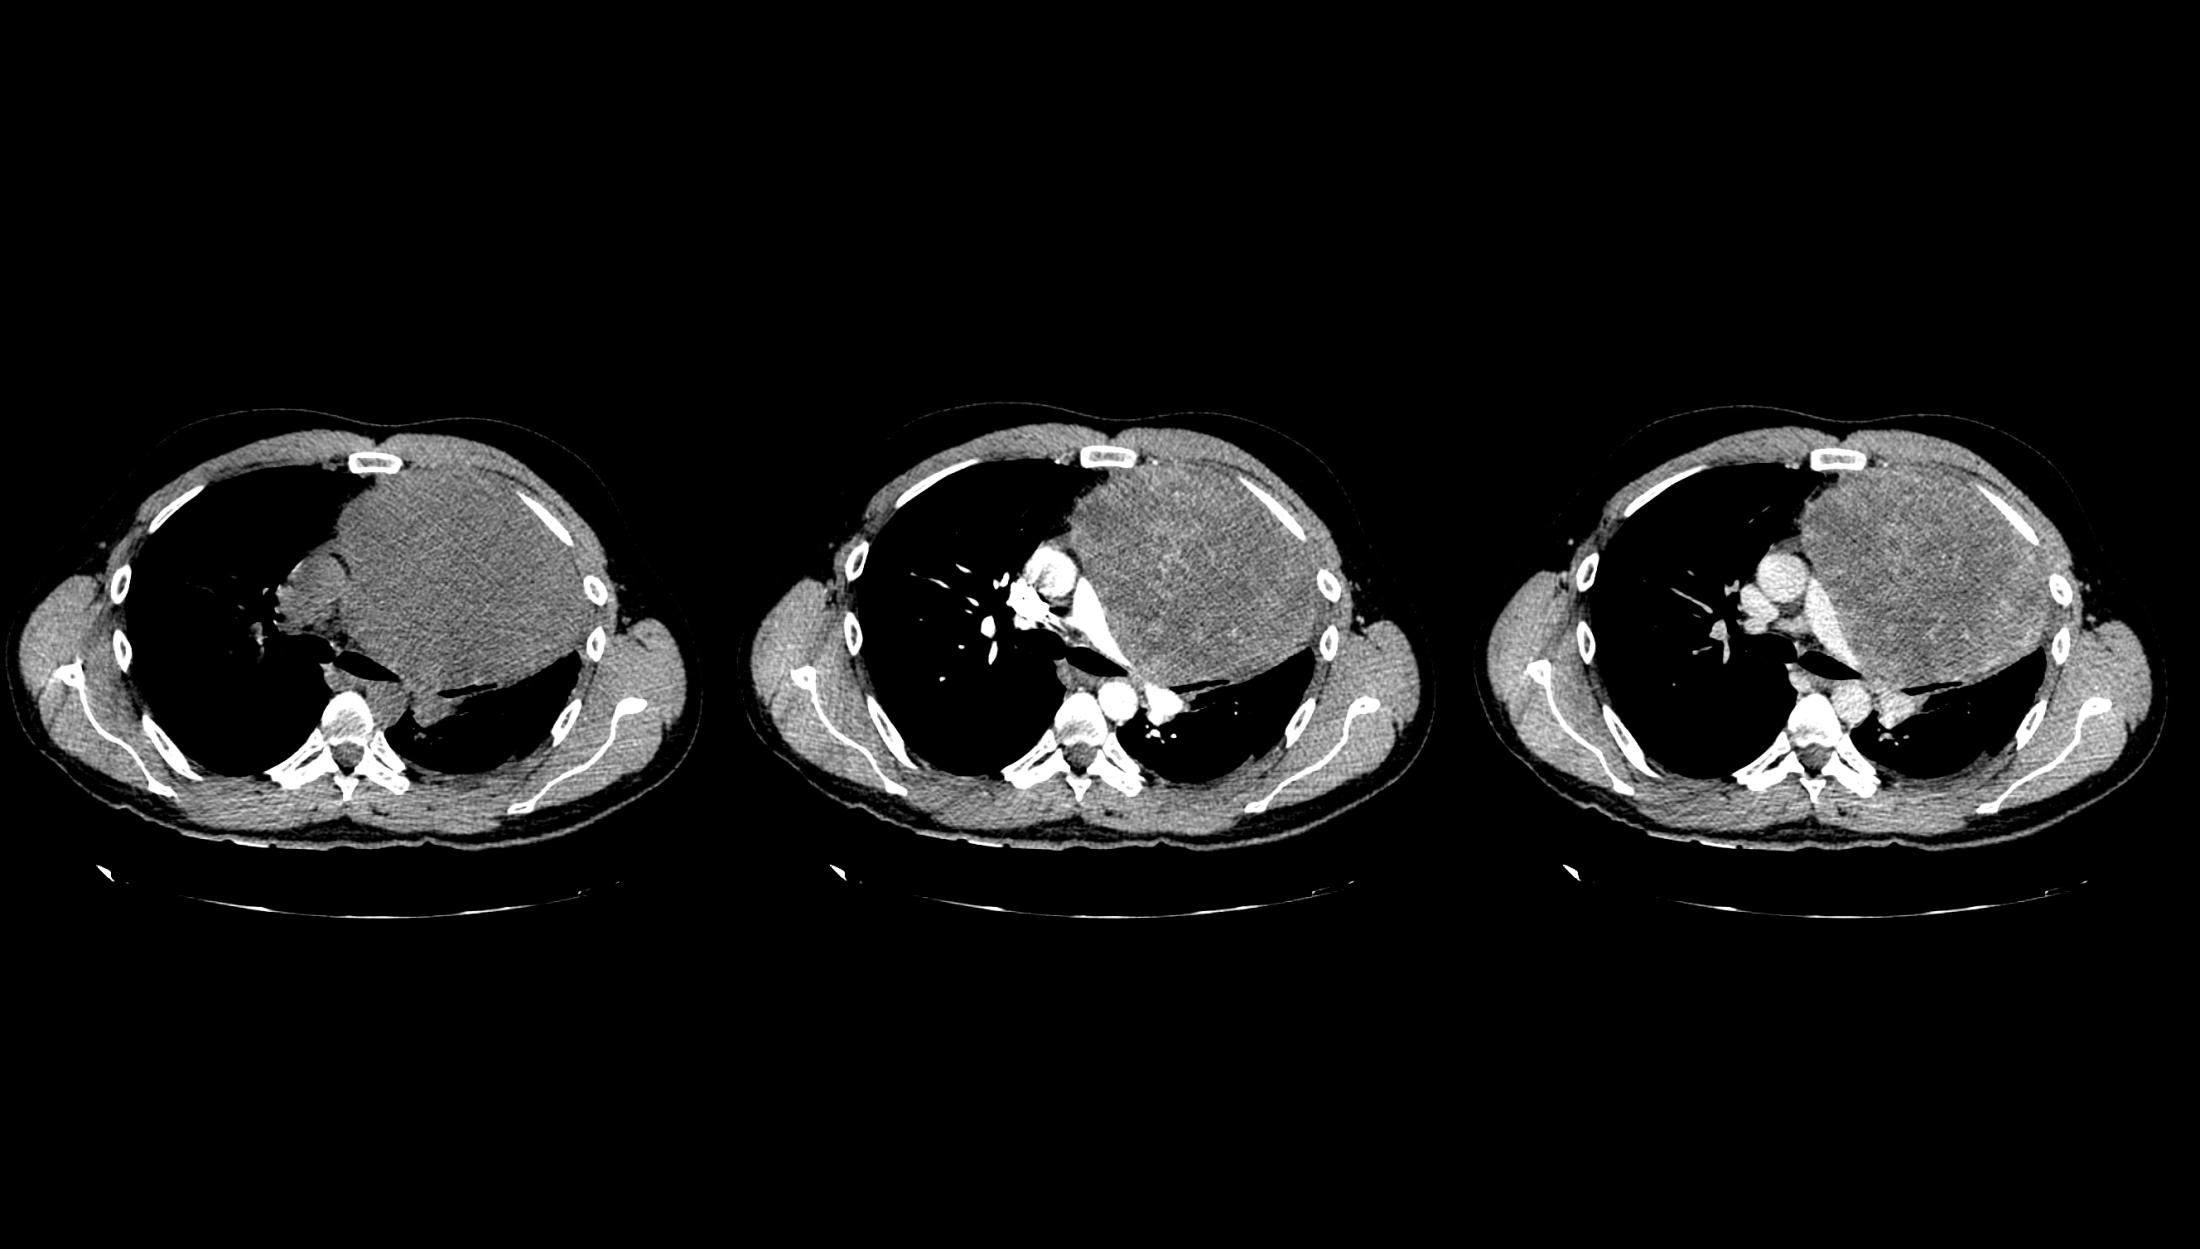

图3 轴位成像显示先前识别的病变表现不均匀性,主要呈现周边强化,以及中央低密度区域,提示坏死;还可见右肺动脉受压

后前位胸片显示左肺周围病变,伴有对侧气管移位和心缘剪影征阴性,同时由于对侧肺代偿性过度充气导致左半膈肌升高。侧面投影显示胸骨后间隙占位,并伴“脊柱征”。增强CT显示先前识别的病变表现不均匀性,主要呈现周边强化,以及中央低密度区域,可能表明有坏死。其位于前纵隔内,不浸润邻近组织,但支气管血管结构向对侧移位。此外,可以观察到右肺动脉受压,同时存在胸腔积液